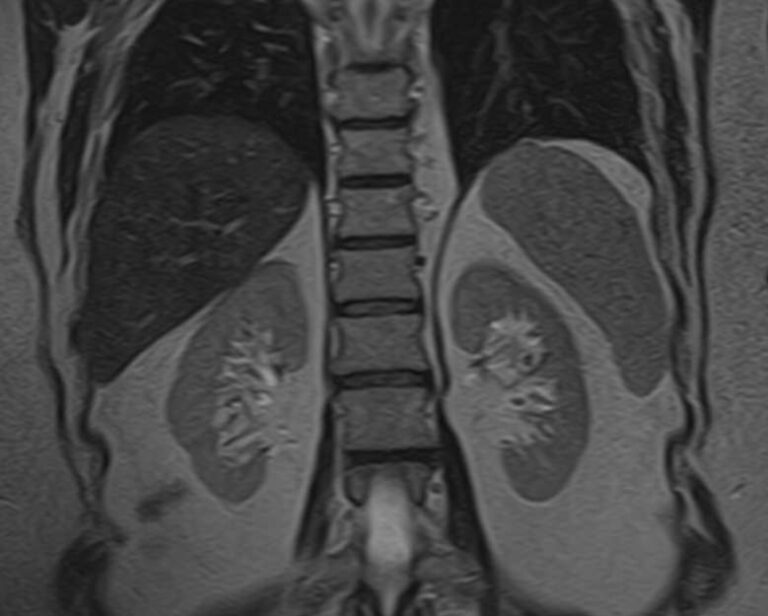

Надпочечники – это парные эндокринные органы небольшого размера, расположенные в слое жировой ткани над обеими почками. Каждый надпочечник вырабатывает важнейшие гормоны для регуляции обмена веществ, работы репродуктивной системы и адаптации организма к окружающей среде:

Магнитно-резонансная томография является наиболее точным и информативным методом обследования надпочечников с целью выявления различных заболеваний. Клиника «Доступная медицина» располагает новейшим томографом экспертного уровня TOSHIBA VANTAGE TITAN 1,5 Тесла, который обеспечивает высокую точность и достоверность результатов исследования.

Методика подразумевает послойное сканирование анатомической зоны надпочечников с последующей цифровой обработкой полученных данных для создания трехмерных изображений. Для более детальной визуализации патологических очагов, особенно при подозрении на развитие опухолевых образований, применяется контрастное усиление.

Контрастирование осуществляется путем внутривенного введения препарата, содержащего соли гадолиния. Благодаря способности контрастного вещества фиксироваться в патологических очагах возможно диагностировать опухоли размером от 1 мм. Метод позволяет выявлять опухолевый процесс на начальной стадии, что значительно улучшает прогноз в плане лечения и выздоровления.